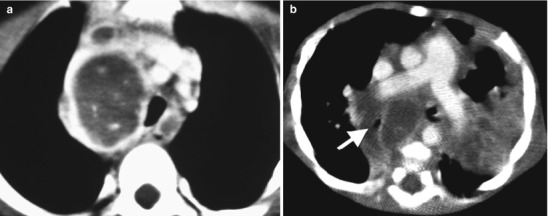

Lymphadenopathy (present in 92 %) with or without a visible Ghon focus is the radiographic hallmark of TB infection and usually involves the hilar and paratracheal regions. The Ghon focus may be too small to be radiographically visible but can also undergo caseation and calcify (Fig. 13.17). Disease progression may occur at the site of Ghon focus, within the regional lymph nodes, or following disease spread (Fig. 13.18). Parenchymal involvement in primary pulmonary TB most commonly appears as homogeneous consolidation, although it can appear patchy, linear, nodular, and mass-like. Caseation necrosis, liquefaction, or calcifications can be seen within the consolidation and can progress into extensive lung damage (Marais et al. 2004) (Fig. 13.19). Enlarged and edematous hilar, paratracheal, and subcarinal lymph nodes may cause compression of the adjacent bronchus and can lead to hyperinflation or atelectasis of the affected lung segment. Contrast-enhanced CT shows a characteristic appearance consisting of central areas of low attenuation with peripheral rim enhancement and obliteration of perinodal fat (Kim et al. 1997) (Fig. 13.20).

Fig. 13.20.

Progression of lymph node disease. Image (a) demonstrates an enlarged right paratracheal lymph node effacing the trachea, with central hypoattenuation and peripheral contrast enhancement. Image (b) shows extensive subcarinal lymph nodes effacing the bronchi, especially the right mainstem bronchus (white arrow)